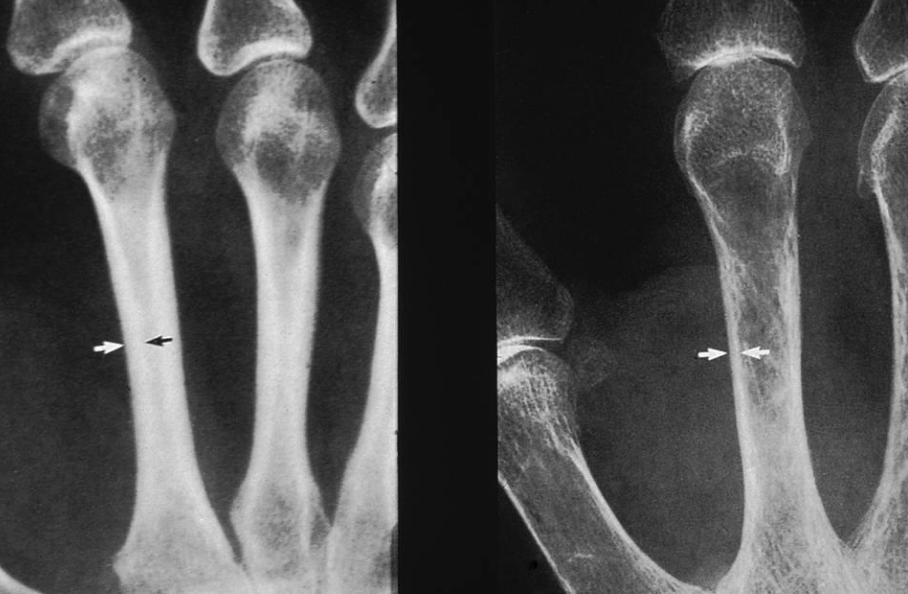

A

Rheumatoid Arthritis with ulnar deviations